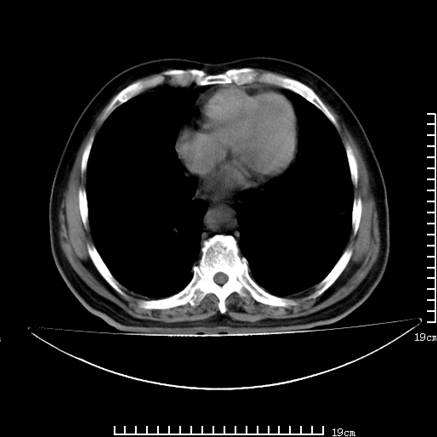

以下是引用zsl6918在2008-7-19 21:53:00的发言:[br]胆总管结石并胆系感染,胆囊切除术后改变。

以下是引用sch2008在2008-7-19 22:03:00的发言:[br]肝内胆管及胆总管积气,并胆总管结石,考虑;胆囊切除术后,胆系感染

以下是引用xinliheng001在2008-7-19 21:59:00的发言:[br]胰头段胆管结石肝内外胆管扩张积气。

以下是引用liaoqiang在2008-7-19 22:26:00的发言:[br]胆总管结石伴胆系感染。